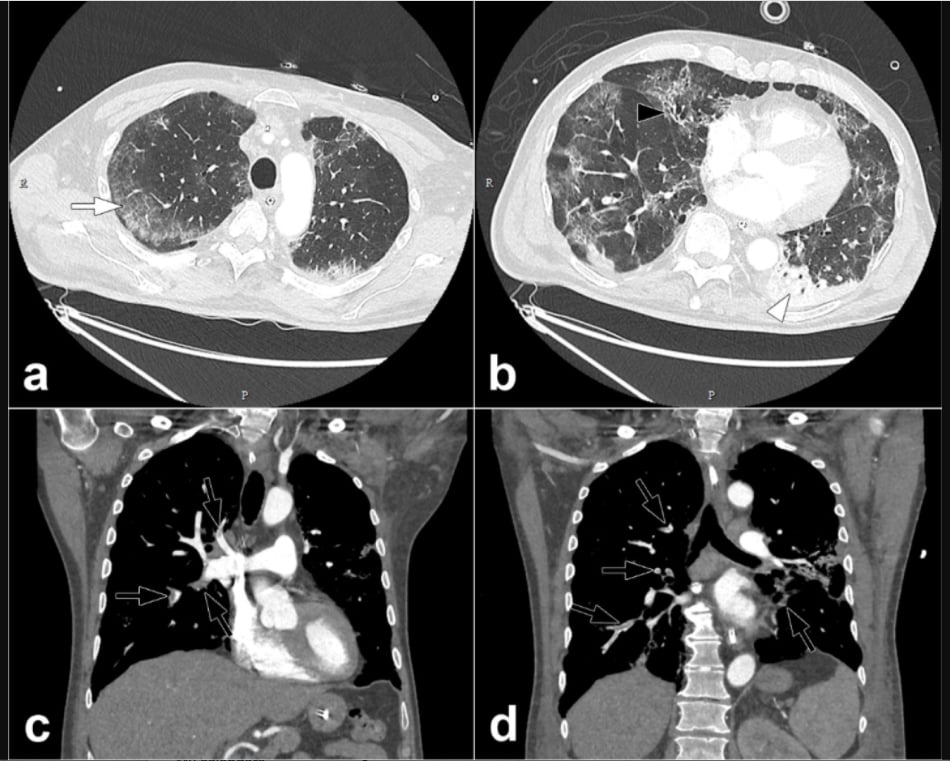

This photo gallery shows the variety of radiological presentations of COVID-19 (SARS-CoV-2) in medical imaging, including computed tomography (CT), radiograph X-rays, ultrasound, echocardiograms and magnetic resonance imaging (MRI). The radiology images show examples of typical COVID pneumonia in the lungs and the numerous complications the virus causes in the body in multiple organs, including the brain, kidneys, heart, abdomen and vascular system.